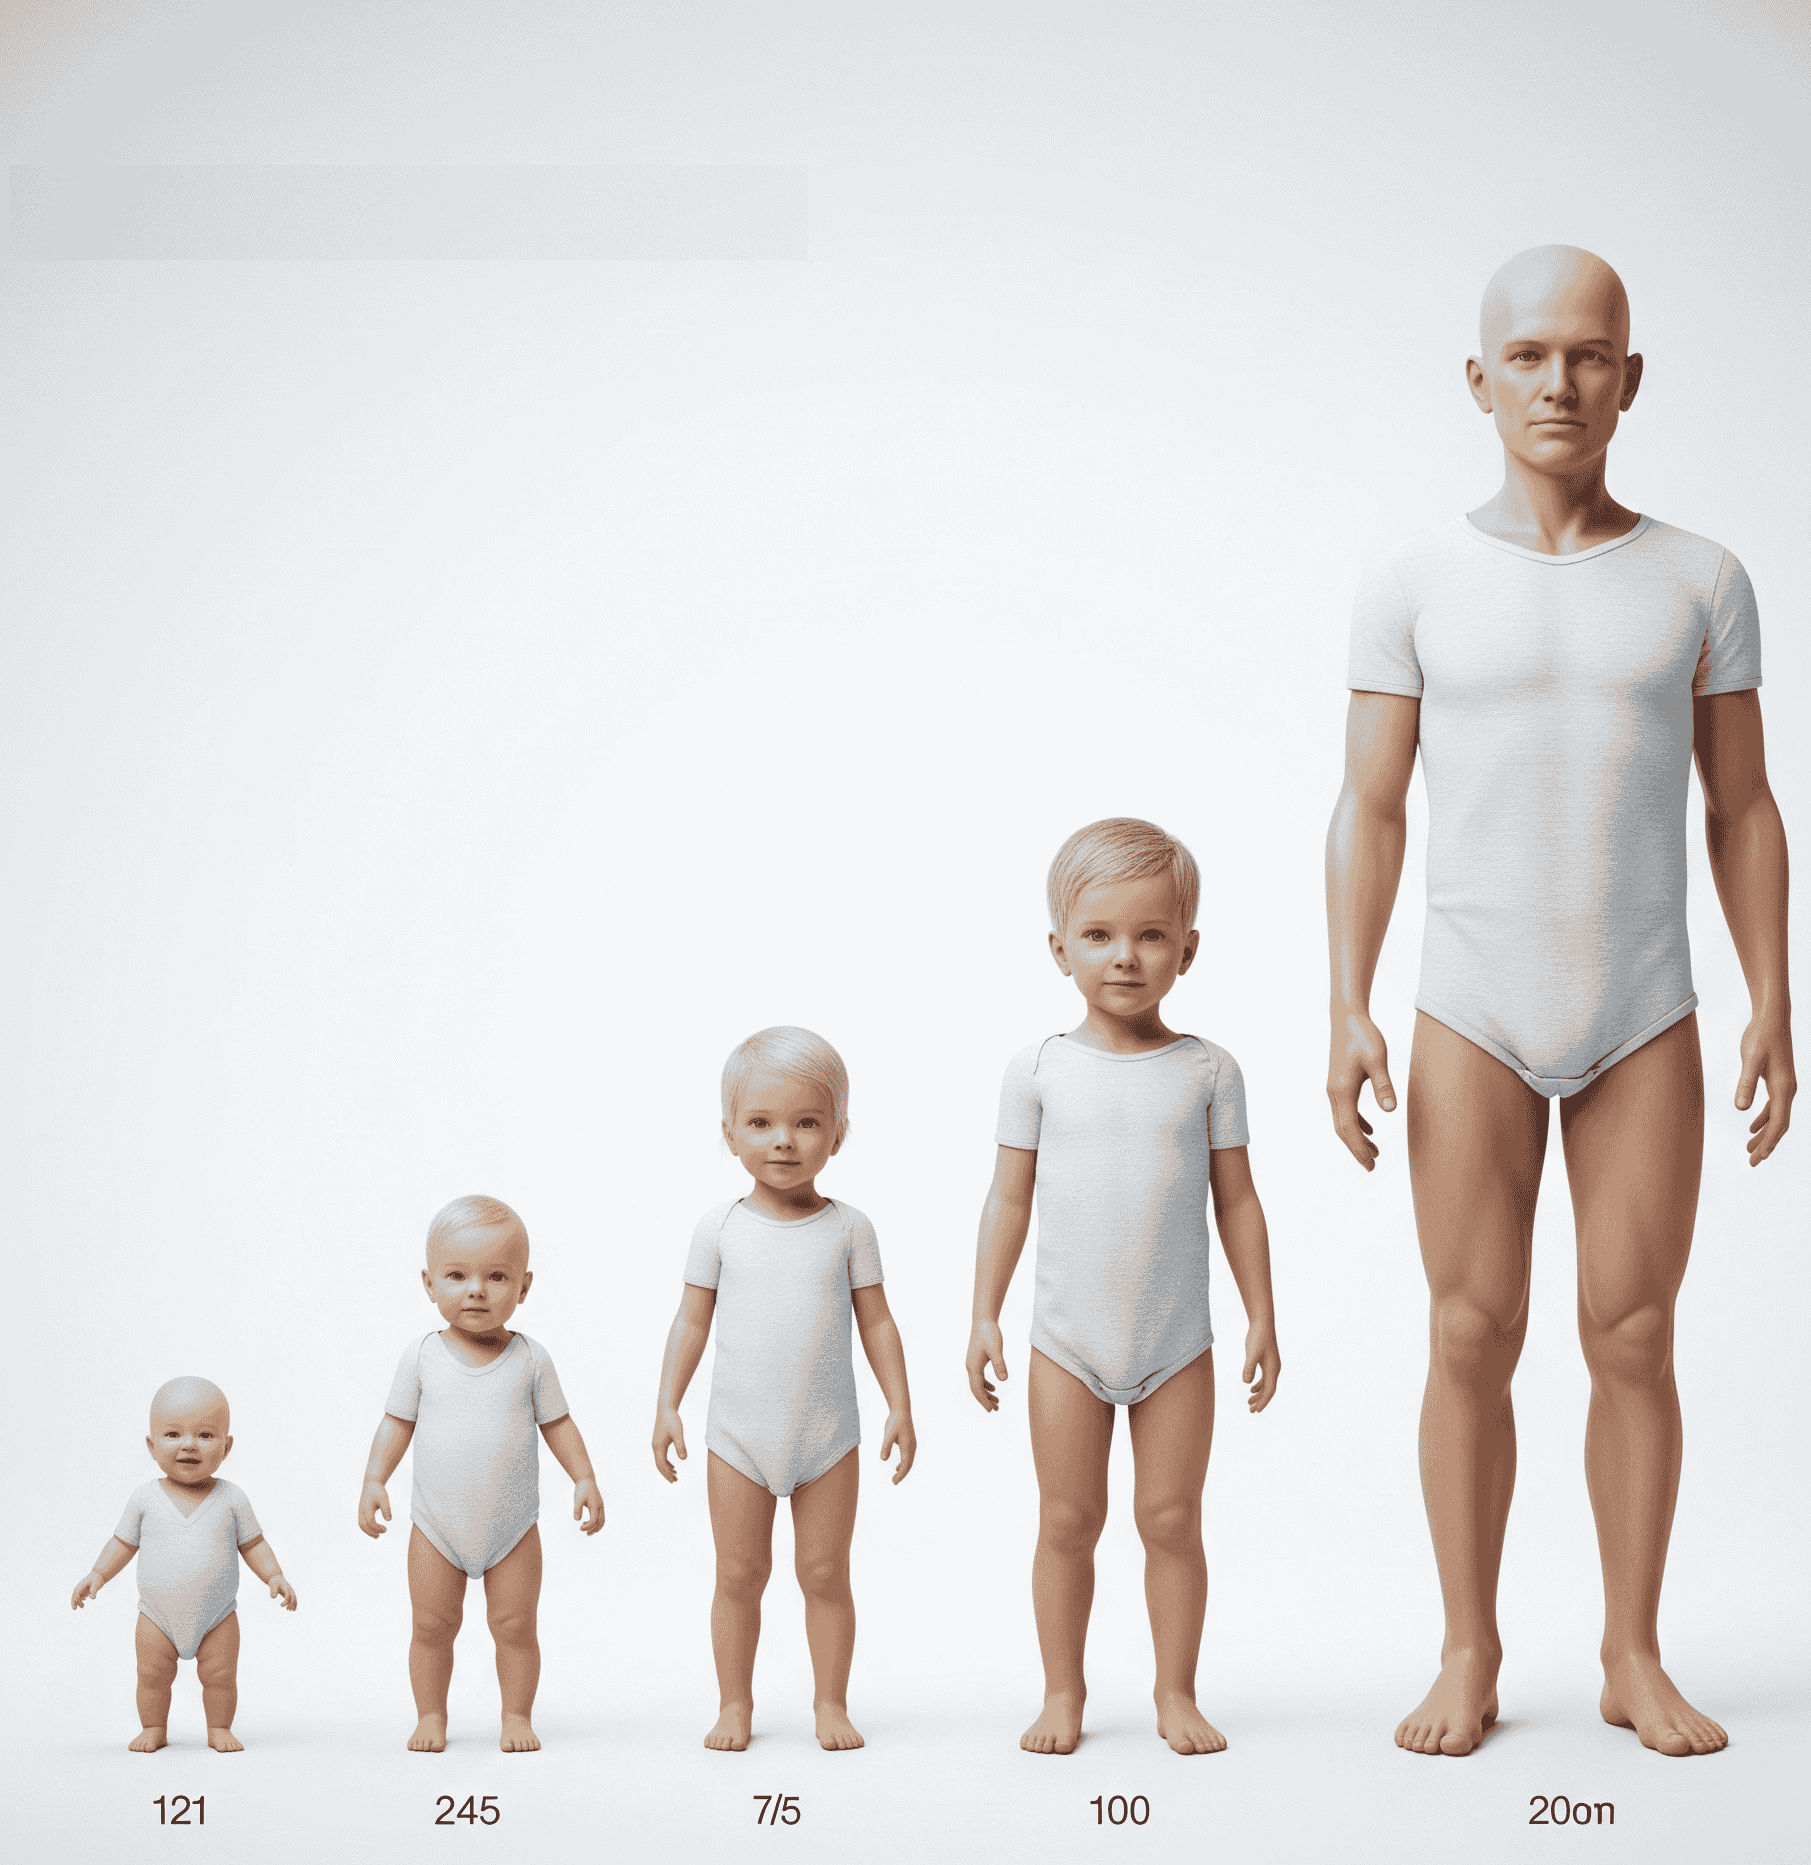

Journal of Pediatric Development & Growth Science

Journal of Pediatric Developmental & Growth Science is a peer-reviewed academic publication dedicated to advancing knowledge on the biological, psychological, and environmental factors that influence child development and growth.